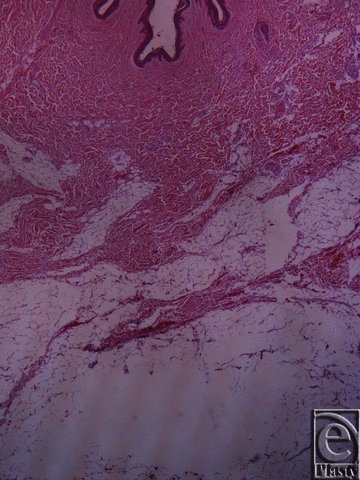

![]() |

| Figure 6. Inframammary crease. Hematoxylin and eosin ×25. The fibrocollagen bundles of the subdermal tissue are attached to the dermis with a broad base. |